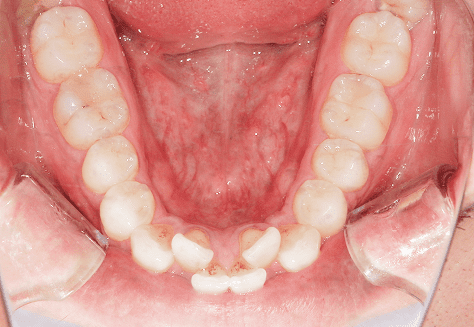

M.M

治療前

治療後

主訴

嚙み合わせが悪い。八重歯が気になる。

診断

叢生・反対咬合

年齢/性別

10代/女性

抜歯部位

非抜歯

使用装置

インビザラインファースト→インビザラインフェーズⅡ(部分的にワイヤーにて処置)

保定装置

上下ビベラリテーナー

料金

初回資料採得・・・・・・・30,000円

診断料・・・・・・・・・・0円

動的治療終了時資料採得・・5,500円 -

基本料金

円ファースト時:450,000円

フェーズⅡ時:240,000円 -

診察料金

ファースト時:0円×16回

フェーズⅡ時:5,500円×9回

ワイヤー併用時:8,800円×2回 -

治療期間

2年7カ月